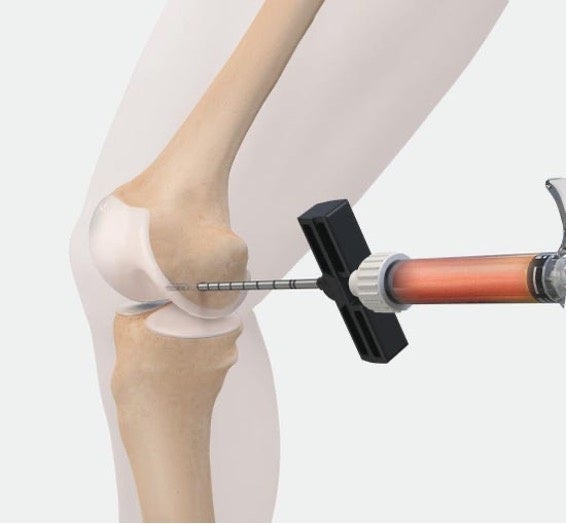

IOBPはBML(Bone marrow lesion、骨髄異常陰影)に対する治療であり、体への負担が少ない手術です。骨の中にPRPや細胞などの生物由来材料を専用の医療機器で注入し、骨の治癒や再生を促します。

IOBPは骨の中に「Angel cPRP/BMCシステム」などで調整したPRP(多血小板血漿)やBMC(濃縮骨髄液)などの生物由来材料を専用の医療機器で注入し、骨の治癒や再生を促す治療です。

外科的治療として、患者さんの腸骨(骨盤の骨)から採取した骨髄液を専用の医療機器で濃縮し、BMCを調整し、骨内に注射器で注入します。また、BMCの代わりにPRPを注入する場合もあります。 |

外科的治療として、患者さんの腸骨(骨盤の骨)から採取した骨髄液を専用の医療機器で濃縮し、BMCを調整し、骨内に注射器で注入します。 |